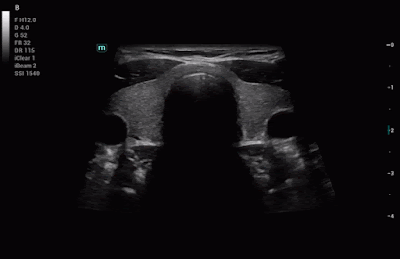

Soluciones integrales de imágenes impulsadas por ZST +

La plataforma ZST + es una innovación extraordinaria, que representa una evolución de los ultrasonidos. Transformar las métricas de ultrasonido de formación de haz convencional a procesamiento basado en datos de canal. Supera la limitación de compensación tradicional entre la resolución espacial, la resolución temporal y la uniformidad del tejido, y ofrece una calidad de imagen excepcional para infinitas soluciones de imágenes con mejoras continuas.Diseño ergonomico